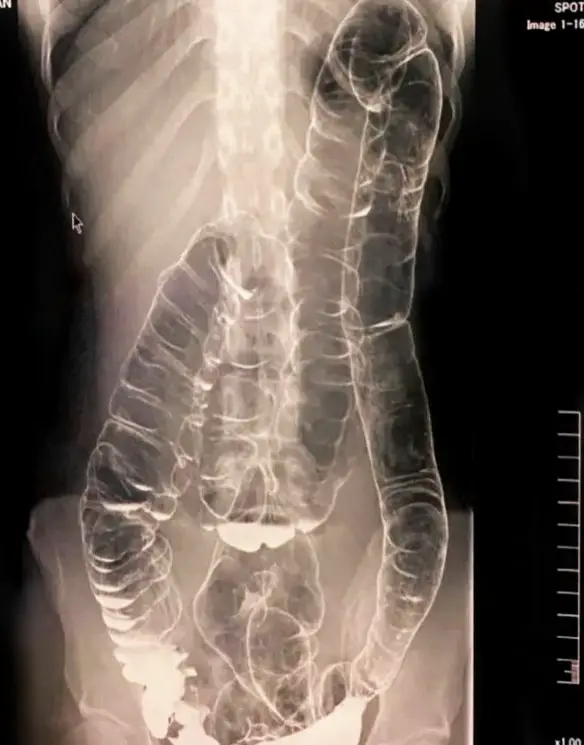

Radiografia che mostra il colon di un paziente donna dopo 19 giorni di costipazione. Ben visibile la severa distorsione del profilo intestinale, a causa dell’eccessiva quantità di Continua a leggere